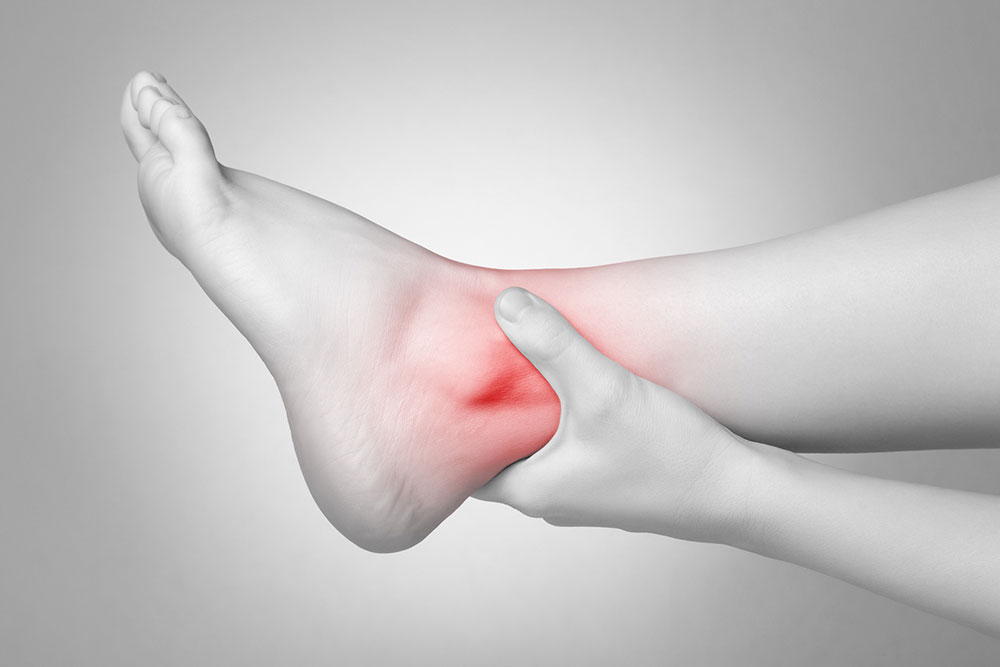

Causes and Home Remedies for Heel Pain

An extremely common complaint, heel pain has several common causes. It is vital to make an accurate diagnosis of the cause of the symptoms in order to get appropriate and timely treatment that is directed at the exact cause of the problem. Once the source of the heel pain is clear, a more targeted treatment plan can help in a speedy recovery. Furthermore, knowing the right and the exact cause of the symptoms may help in taking steps to prevent the condition from reoccurring. Below is some information about the common causes of knee pain and the treatment and remedial options.

Heel pain can sometimes be caused by an injury like a fracture or a sprain. The most common causes of heel pain are caused by medical conditions like:

- Achilles tendinitis – The Achilles tendon attaches the calf muscles to the heel bone. Overuse or stress of this muscle can cause wear and tear in this tendon, causing severe pain at the back of the heel.